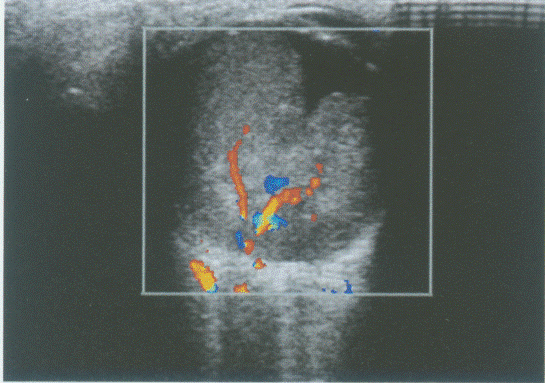

176、单项选择题

临床资料:女性,25岁,自述心悸,多汗,食欲亢进,体重减轻6个月余,发现颈部增粗1周。临床物理检查:甲状腺对称性增大,随吞咽上下运动,听诊有血管杂音。超声综合描述:双侧甲状腺增大,回声减低,明显不均,内未见囊实性肿物,CDFI:内可见丰富动静脉血流信号,呈"火海"征。见下图及彩图。

超声提示()。

A.结节性甲状腺肿

B.毒性甲状腺肿(原发性甲状腺功能亢进)

C.甲状腺腺瘤

D.甲状腺正常声像图

177、单项选择题